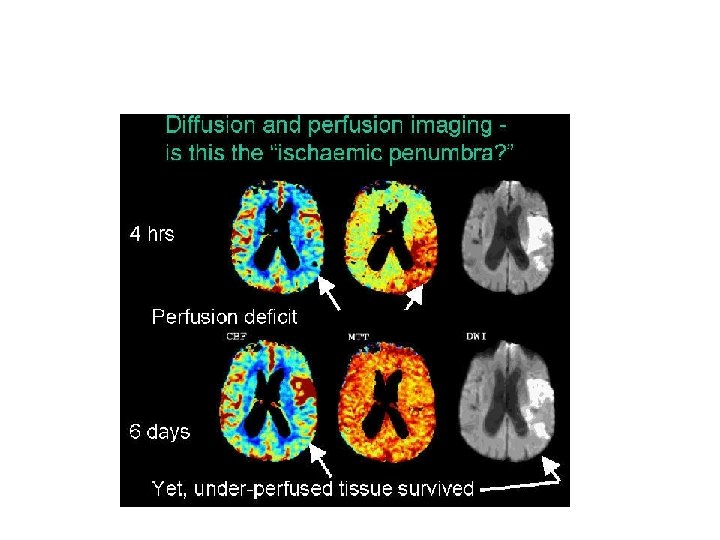

Perfusion MRI Weighted Image